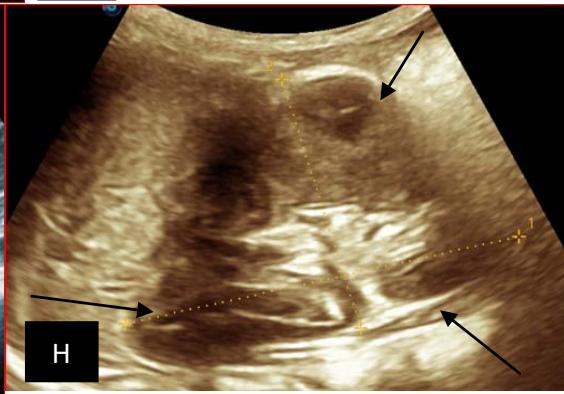

Tshibasu Tshienda et al. Ultra Sonographic Profile of Nephroblastoma at the University Clinics of Kinshasa